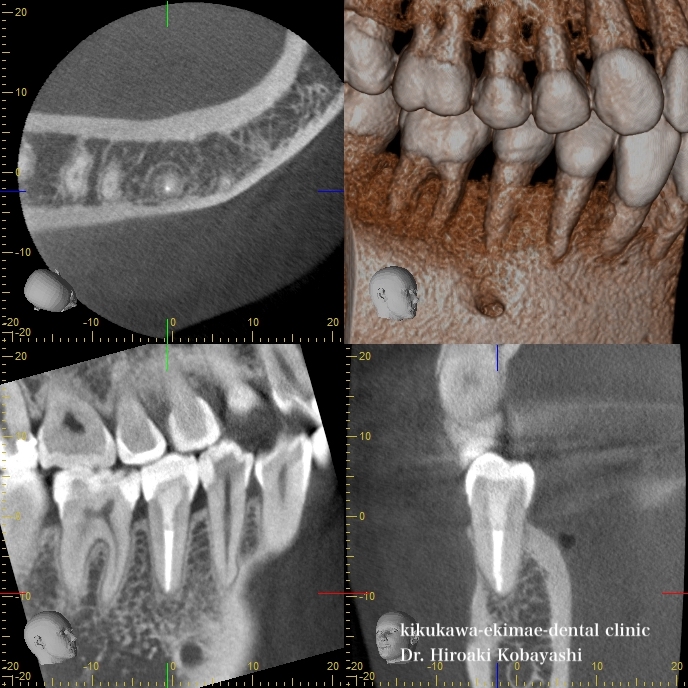

5年前、歯の神経の壊死が起こり、根の尖端に黒い影がりました。 この状態を放置しますと、骨の吸収が大きくなり、抜歯に至ります。   精密根管治療5年後のCTにて確認したところ、根の尖端の影はなくなり、骨の再生が見られます。 根管治療の成功は、精密な根管治療もそうですが、コアや被せ物の接着のクオリティーに依存します。そのためには、口腔内細菌をいかに、感染、再感染をさせないようにする事が非常に重要です。 神経が死んだとしても適切に処置を行えば骨の再生が起こり、歯の延命が可能です。